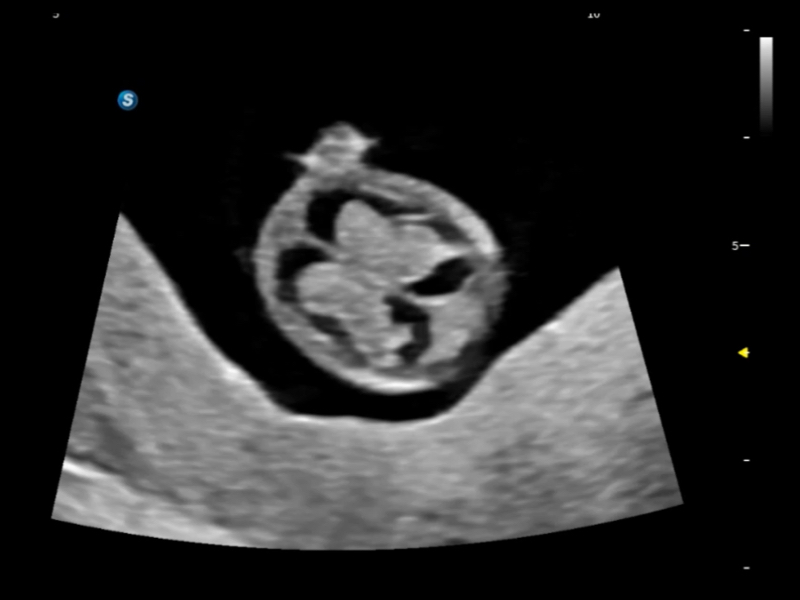

独有场成像发射技术

自适应聚合重建技术

在传统血流的基础上优化扫查和算法策略,能够更好的抑制组织信息,提炼红细胞运动信息,得到更高帧频,高灵敏度和分辨率的血流信号,还原更真实的血流动力学。